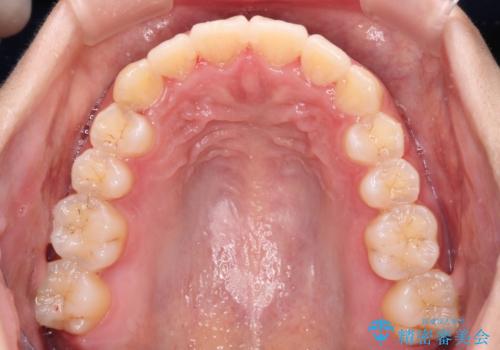

前歯のデコボコをインビザラインでスッキリと

- 上下前歯のデコボコを気にして来院された患者様です。

デコボコを解消する過程で、歯列の拡大により口元が突出する可能性があったため、4本の親知らずを抜歯しておき、歯列全体が後方に移動するように設計し、インビザラインにて矯正治療を行うこととしました。

日々の装着時間をしっかりと守って治療の臨んでくださったため、治療前のシミュレーションに近い形で矯正治療を進めて行くことができました。